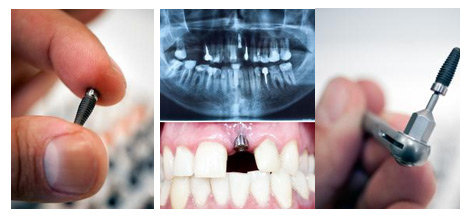

据了解,国内口腔医疗机构使用的种植体大多是依靠进口。一颗种植牙主要分成两个部分:用于在牙槽骨内“打桩”的种植体(包括钉子、基台等)和牙冠(即义齿)。